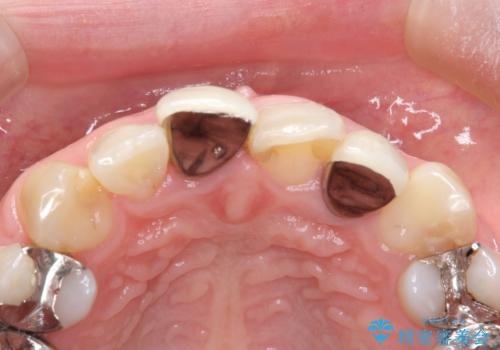

- 他院で装着された保険の前歯のかぶせ物が、他と歯と馴染まないので、自然な歯にしたいとのことで来院されました。

右上の1番目の歯の保険のかぶせ物と金属の土台を、ファイバーコアとオールセラミックにて再補綴する計画としました。

形態も色調もまわりの歯とは、調和がとれておらず、目立っていました。